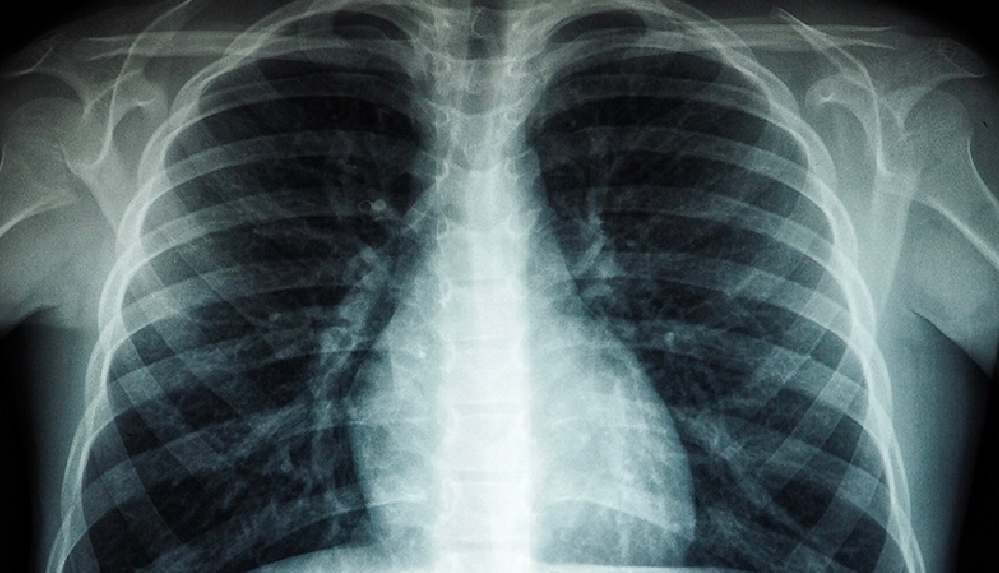

DSÖ: Tüberküloz her yıl 1,5 milyondan fazla kişinin canına mal oluyor